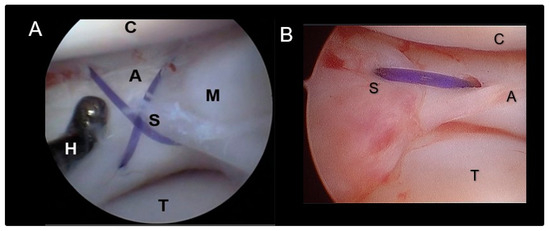

2.3. Meniscal Sutures

2.4. Surgical Stabilization of the Stifle Joint